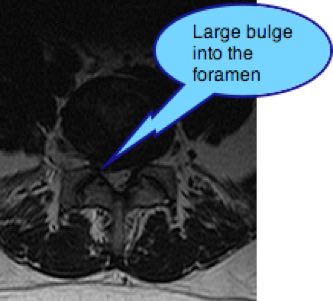

I am 29 y/o, have a 'very large' disk herniation L4/L5 with sciatica for at least a year and half, Was leaning to the opposite side like tower of Pisa for long time, have radiating sciatica from my back to my foot.

I am due a Microdiscectomy in a few months but that's mostly to alleviate leg pain and I'm worried I'm still gonna be stooped forward and struggling to walk even with a crutch. I was advised by a neurosurgeon to avoid chiro as my herniation is so large but I just want to be able to stand up again even if I am leaning to the side and doctors don't seem to give me any answers.